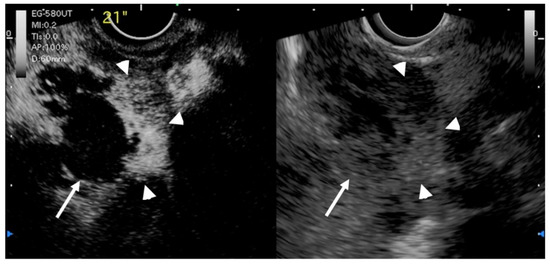

- Muguruma, N.; Okamura, S.; Okahisa, T.; Shibata, H.; Ito, S.; Yagi, K. Endoscopic sonography in the diagnosis of xanthogranulomatous cholecystitis. J. Clin. Ultrasound. 1999, 27, 347–350. [Google Scholar] [CrossRef]

| Xanthogranulomatous cholecystitis | focal or diffuse | smooth | mixed hyperechoic and hypoechoic echotexture | irregular or disrupted |